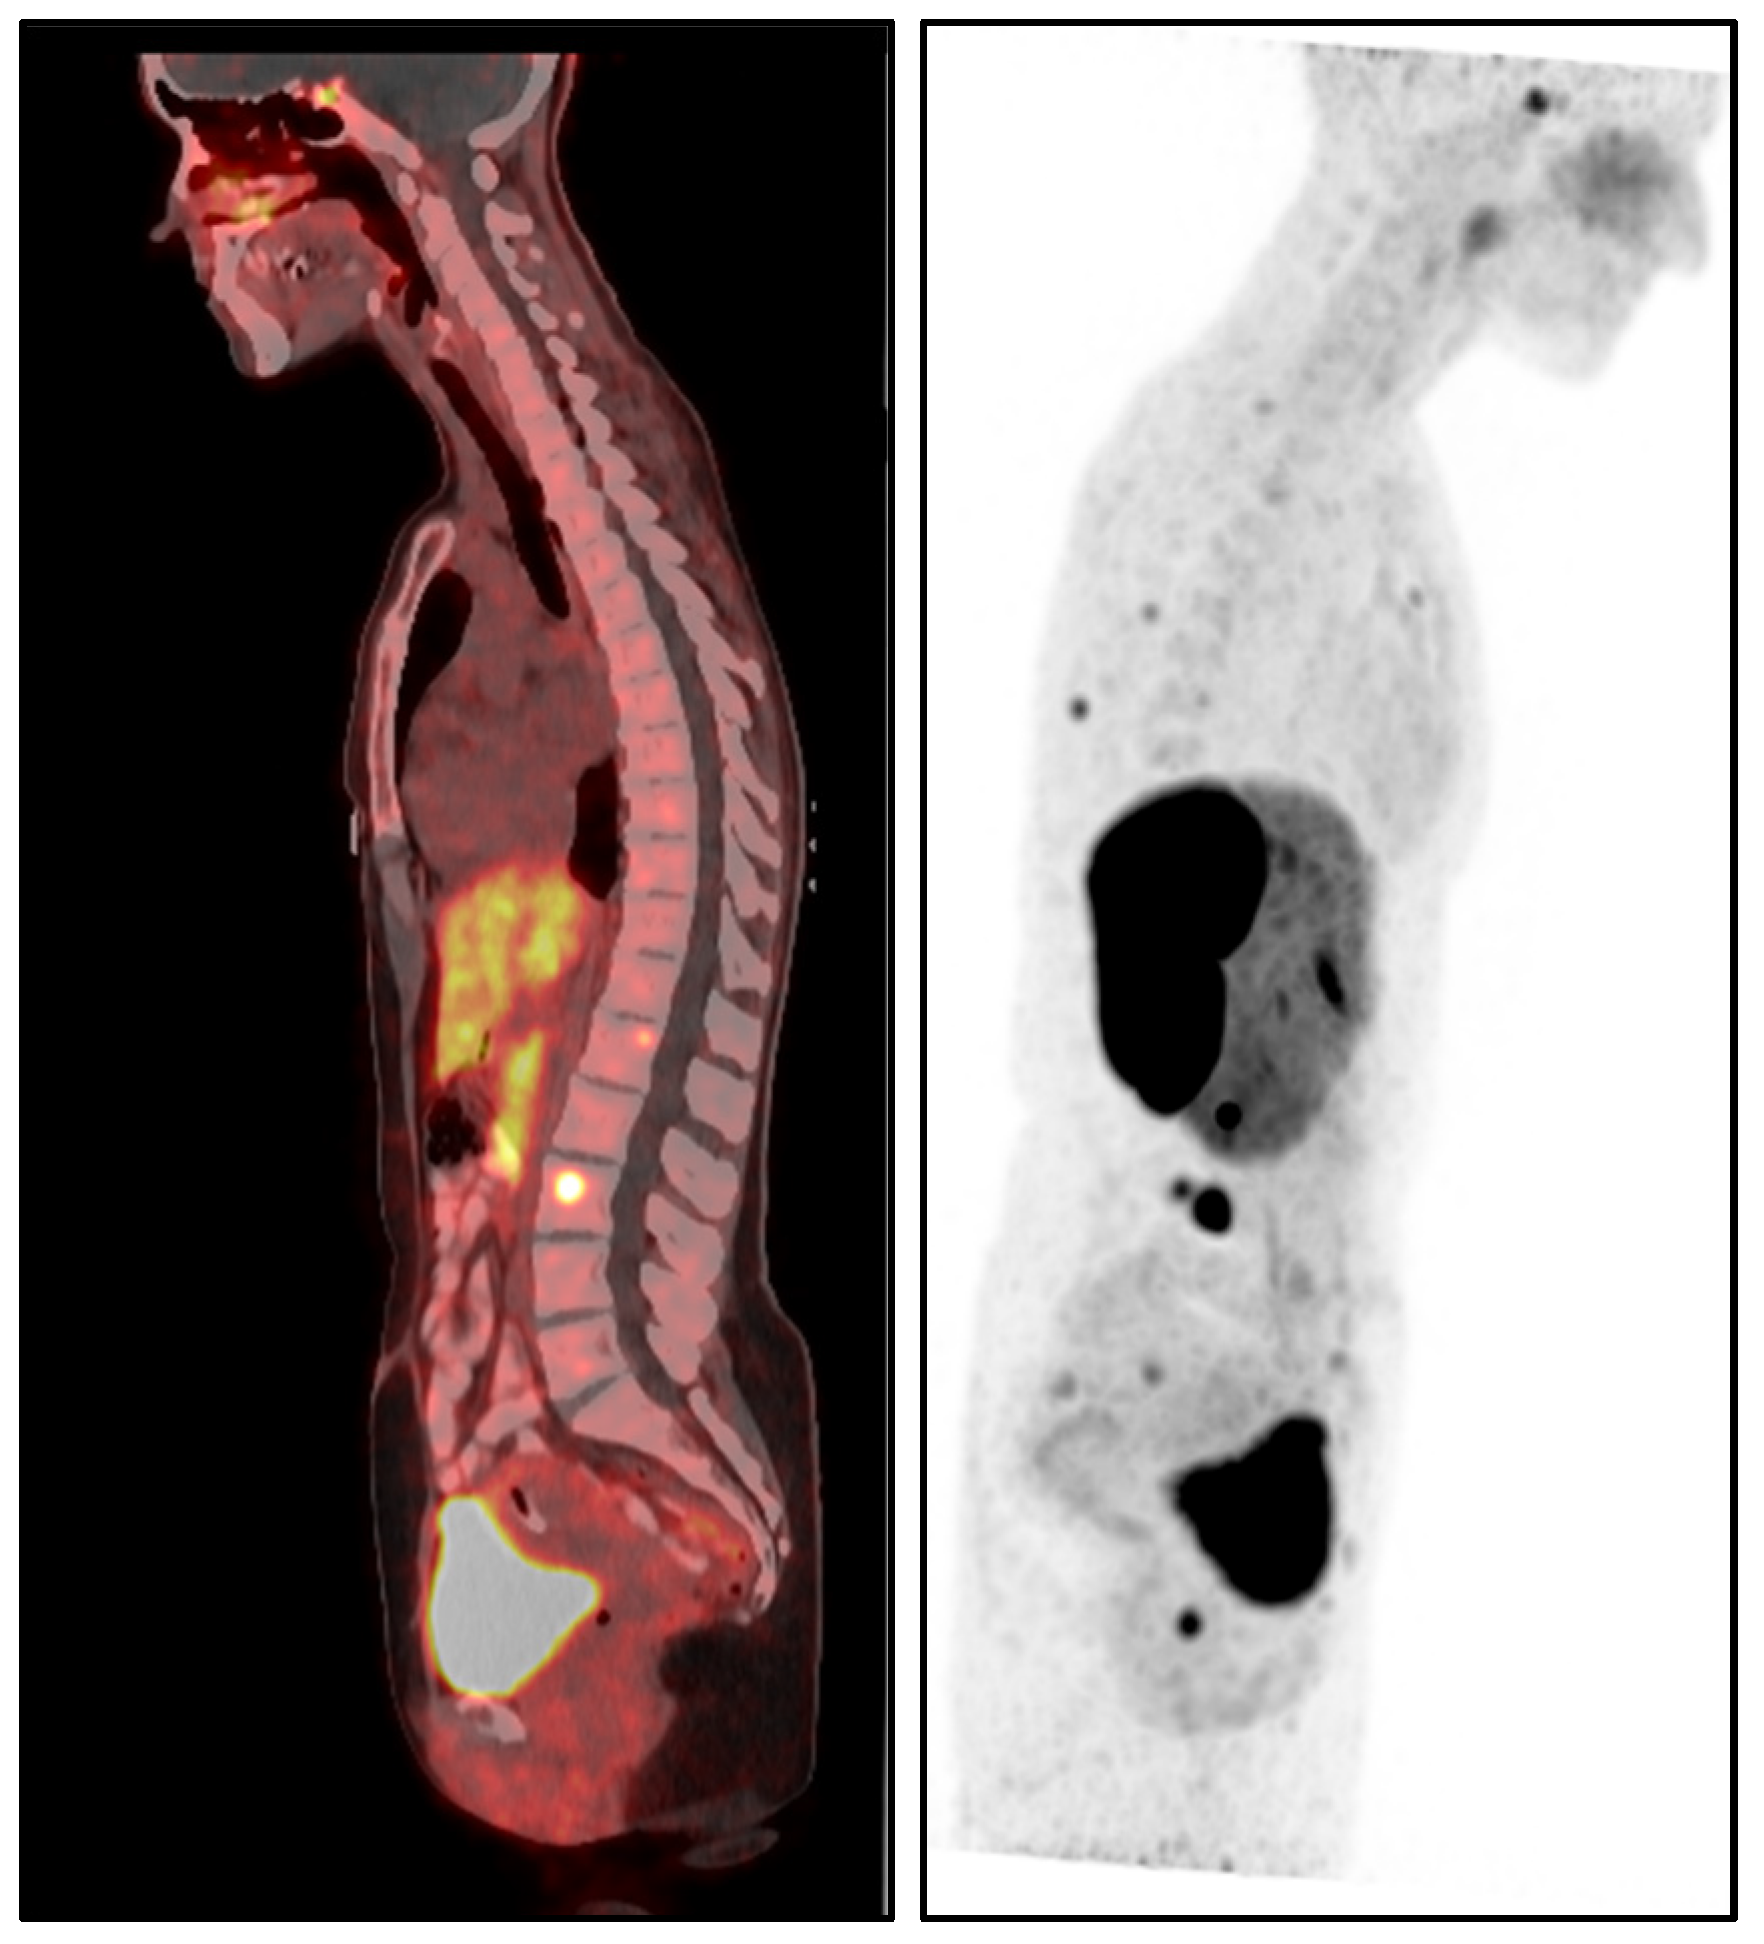

• Increased myocardial signal intensity on T2-STIR sequences (ratio 3:1), suggestive of myocardial edema.

T1 and T2 mapping sequences were not acquired, which represents a limitation in tissue characterization. Nevertheless, these findings were consistent with acute myocarditis according to the 2018 revised Lake Louise criteria (Figure 2 and Figure 3).

Early recognition and accurate diagnosis of myocarditis are critical to initiating timely management and preventing potential long-term cardiac sequelae. Diagnosing drug-induced myocarditis, especially when triggered by bisphosphonates like ZA, poses significant challenges due to nonspecific symptoms and the wide range of potential causes. In this case, CMR was pivotal, showing increased myocardial signal intensity on T2-STIR sequences (signal intensity ratio 3:1) and subepicardial late gadolinium enhancement in the lateral wall of the left ventricle (Figure 2, Figure 3 and Figure 4). These findings are consistent with acute myocarditis as defined by the 2018 revised Lake Louise criteria [22].

Although T1 and T2 mapping was not performed, precluding quantitative tissue characterization, T2-STIR still provided meaningful visual evidence of edema. While the technique has known limitations—such as motion artifacts and lower spatial resolution—it remains useful in the clinical setting. Notably, no inferior wall subepicardial LGE was observed, reinforcing a non-ischemic distribution consistent with myocarditis rather than infarction.

Figure 3. (a,b) Phase-sensitive inversion recovery (PSIR) sequence, 4-chamber view. Subepicardial late gadolinium enhancement (LGE) is seen in the lateral wall (arrows), supporting the diagnosis of myocarditis.